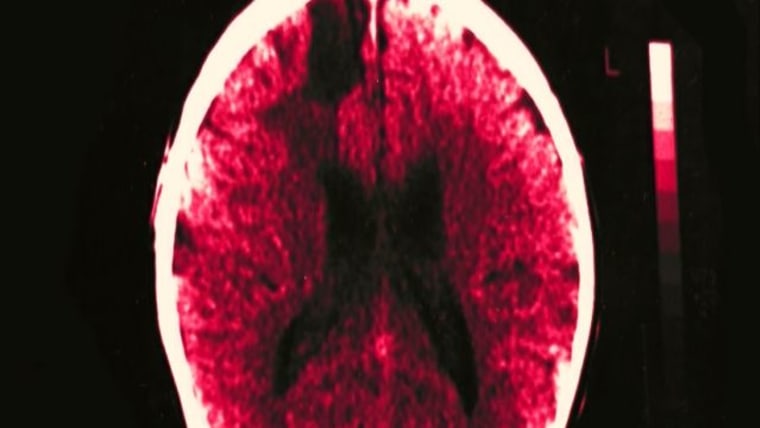

Tumor Atlas Combats Deadly Cancer

A new project from the Allen Institute for Brain Science could help understand deadly glioblastoma tumors. KING's Jean Enersen reports.